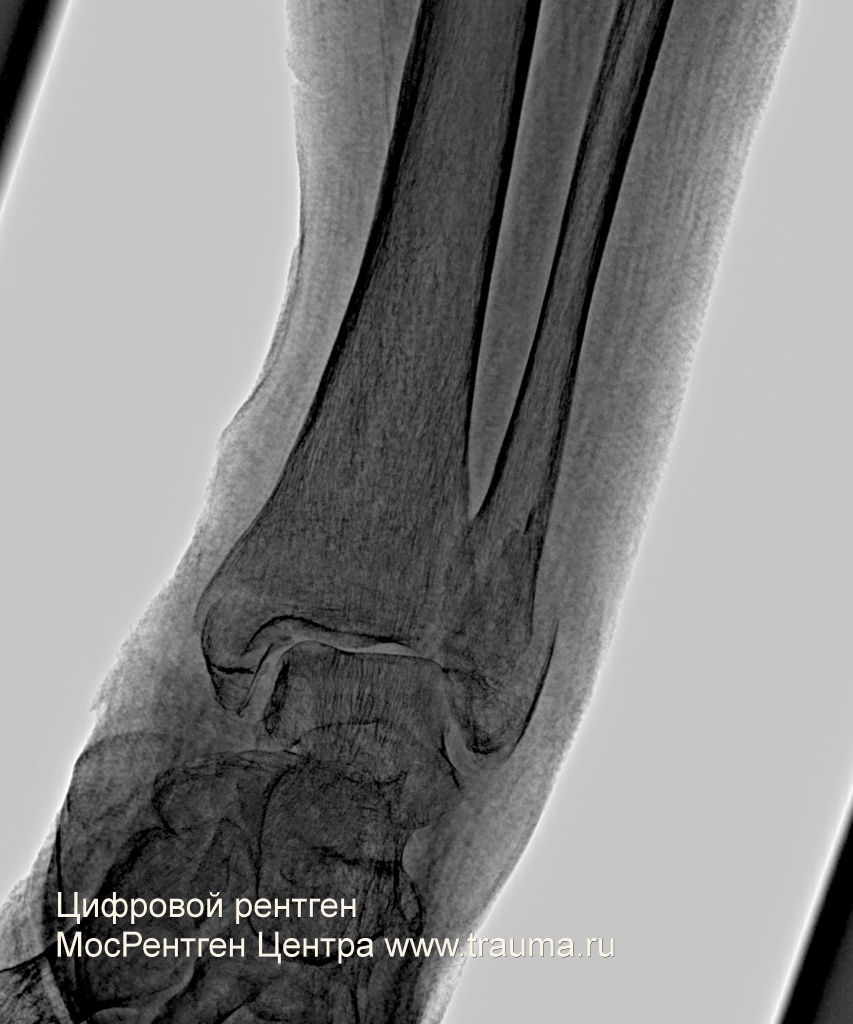

Ж 78, 130 кг. 4 инсульта в анамнезе.Травма 25.09.2018. Доставлена в 36 ГКБ г. Москвы, где произведено вправление подвывиха стопы, наложена U-образная гипсовая повязка со стопой. На контрольной рентгенограмме подвывих стопы был вправлен. При выписке рентгенконтроля не делали, отправили с лонгетной временной гипсовой повязкой. На контрольной рентгенограмме в травмпункте 08.10.2018 видно смещение отломков, значительный подвывих стопы кнаружи. От госпитализации пациентка отказалась.

Снимок в наложенном гипсе в прямой проекции. Красными стрелками показаны движения голени и стопы, в результате которых произошел подвывих. Ходить на такой стопе было бы невозможно - стопа при нагрузке будет уезжать кнаружи.

На рентгенограмме в гипсовой повязке: перелом лодыжек, фрагмента заднего края большеберцовой кости, повывих стопы кнаружи слева. Костная плотность снижена.

На боковой проекции, к счастью, подвывиха кзади нет.

На контрольной рентгенограмме сохраняется подвывих 3 мм. С учетом остеопороза от дальнейших попыток решено воздержаться.